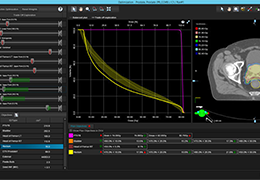

ART-Plan™ Artificial Intelligence Contouring